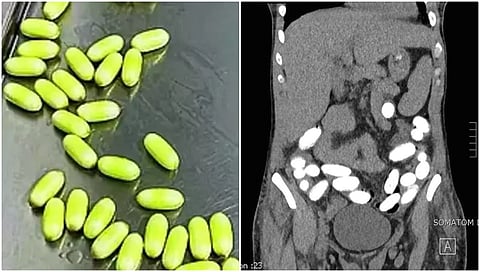

ಆರೋಪಿಯು ಫೆಬ್ರವರಿ 9ರಂದು ದುಬೈನಿಂದ ಎಮಿರೇಟ್ಸ್ ವಿಮಾನದಲ್ಲಿ ಬೆಂಗಳೂರಿಗೆ ಬಂದಿದ್ದಾಗ ಆತನನ್ನು ಡಿಆರ್ಐ ಅಧಿಕಾರಿಗಳು ವಶಕ್ಕೆ ಪಡೆದಿದ್ದರು. ಪ್ರವಾಸಿ ವೀಸಾದಲ್ಲಿ ಭಾರತಕ್ಕೆ ಬಂದಿದ್ದ 40 ವರ್ಷದ ಪ್ರಯಾಣಿಕನ ವೈದ್ಯಕೀಯ ಪರೀಕ್ಷೆ ನಡೆಸಿದಾಗ ಆತನ ಹೊಟ್ಟೆಯಲ್ಲಿ ಕೊಕೇನ್ ಇರುವುದು ಪತ್ತೆಯಾಗಿದೆ. ನಂತರ 920 ಗ್ರಾಂ ಕೊಕೇನ್ ನ 91 ಕ್ಯಾಪ್ಸುಲ್ಗಳನ್ನು ವಶಕ್ಕೆ ಪಡೆದಿದ್ದಾರೆ. ಬಳಿಕ ಆರೋಪಿಯನ್ನು ನಾರ್ಕೋಟಿಕ್ ಡ್ರಗ್ಸ್ ಮತ್ತು ಸೈಕೋಟ್ರೋಪಿಕ್ ಸಬ್ಸ್ಟಾನ್ಸಸ್ (ಎನ್ಡಿಪಿಎಸ್) ಕಾಯಿದೆ, 1985ರ ಅಡಿಯಲ್ಲಿ ಬಂಧಿಸಲಾಗಿದೆ.